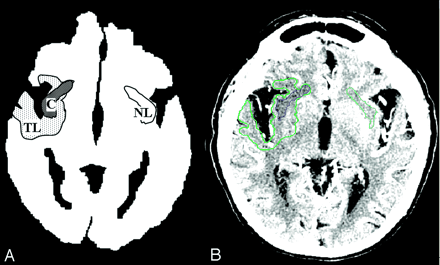

The 3-mm-thick whole-brain CTA source images were evaluated for ischemic regions by identifying areas of relative hypoattenuation. By using a semiautomated software package (Alice; Parexel Corp., Waltham, MA), these ischemic regions of interest were visually segmented (Fig 1) to determine the volume and degree (measured in Hounsfield units) of lesion hypoattenuation. A core lesion was defined as the region of maximal hypoattenuation on a single contrast-enhanced axial section. The mean degree (Hounsfield units) of this lesion was determined. To correct for any within-scan variability, this segmented core was compared with a mirror-image contralateral region of uninvolved tissue (Fig 1). These mirror-image normal regions were matched for gray-white constituents; no CSF spaces, blood vessels, or other volume-averaged tissue were included. Three readers (L.H.S., M.H.L., E.S.R.) who were experienced in the interpretation of stroke CT scans and who were blinded to the patients’ clinical histories, lateralization of symptoms, follow-up imaging and clinical outcomes analyzed the images. All imaging studies were independently interpreted during multiple reading sessions by using optimal window width and center level settings to identify subtle differences between normal and hypoattenuating brain parenchyma (34). Disagreements in ratings were resolved by means of consensus blinded review.

Schematic (A) and contrast-enhanced (B) CTA source images display region-of-interest segmentation. Single-section total lesion volume is the entire region of hypoattenuation on the section containing the core (TL, green). Single-section lesion core is the region of maximal hypoattenuation in the right insula (C, dark blue), compared with normal mirror-image tissue in contralateral left insula (NL, light blue).